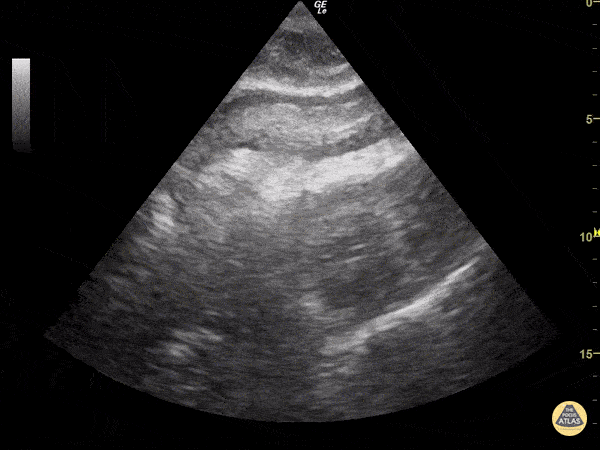

A 83-year-old woman comes to emergency department In cardiac arrest after an episode of severe chest pain. During pulse check we identified PEA (Pulseless Electrical Activity) and performed a CASA Exam. The subcostal view demonstrates a hyperechoic structure in the pericardial space concerning for clot. There is also evidence of cardiac tamponade. Image courtesy of Josiane Almeida